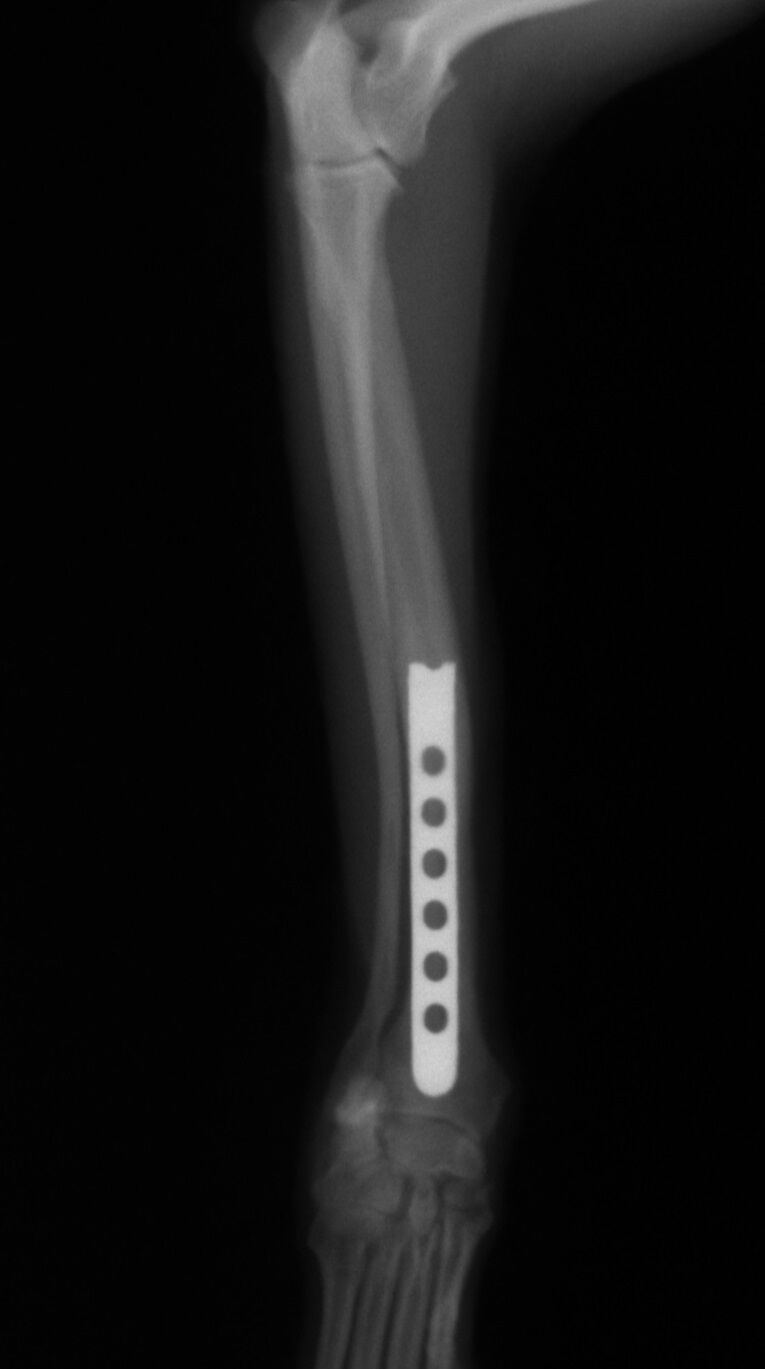

治療はプレートで固定する方法を行いました。骨折位置が橈骨先端に比較的近い位置だったことと、トイ・プードルは骨の増生が悪いことで有名なので少し気を遣う症例でした。プレートはステンレスプレートを用いました。手術直後が下の写真です。